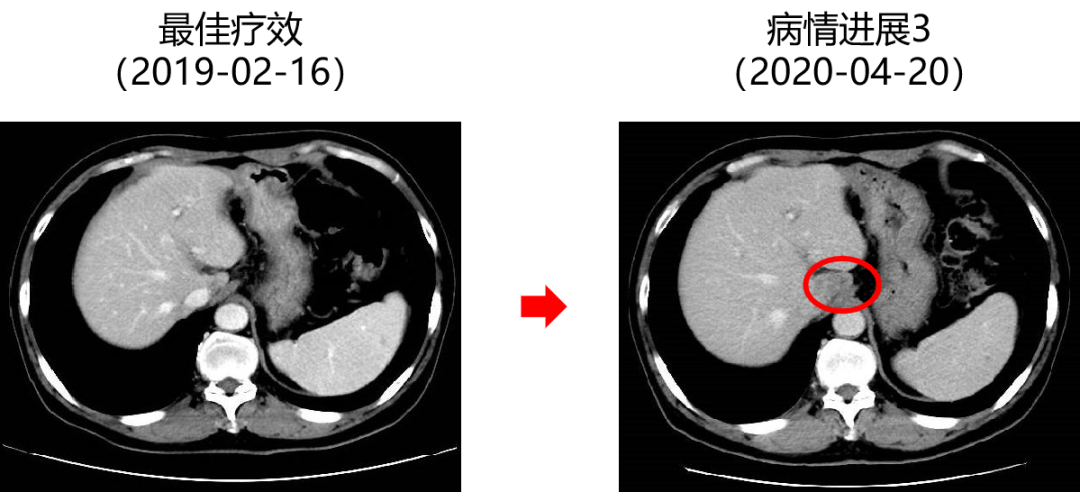

二 病例分享 专家简介 01 基本情况 患者:汪XX,男,63岁。身高 165cm;体重 65kg;体表面积 1.70m2;ECOG 1分。 主诉:反复解黏液血便3天。 对磁共振造影剂过敏,无食物、其他药物过敏史。既往史、个人史、婚育史、家族史均无特殊,无吸烟、饮酒史。 02 初诊病史 现病史:患者2017年3月初无明显诱因下解黏液血便,量中等,为鲜血,反复发作,无恶心、呕血、黑便、腹痛、腹泻、里急后重等不适。遂于2017年3月初就诊我院。 胸、腹、盆腔CT平扫+增强:乙状结肠肠壁明显增厚,肠腔狭窄,增强期强化明显;肝脏多发低密度病灶,增强期不规则强化,考虑乙状结肠癌伴肝脏多发转移。 03 治疗方案 【一线治疗】 2017-06-22 西妥昔单抗+FOLFIRI* Q2W×3 西妥昔单抗 900mg ivgtt D1; 5-氟尿嘧啶 0.6g iv D1,3.5g civ 48h; 亚叶酸钙 0.6g ivgtt D1; 伊立替康 280mg ivgtt D1。 第1疗程结束后黏液血便较前消失,过程顺利,耐受良好,无皮疹、腹泻等不良反应,治疗10疗程,疾病进展。 疗效评估-影像学(部分缓解,PR)。 2017-07-15 乙状结肠癌切除术* 手术记录:肿瘤位于乙状结肠,大小约4cm×3cm,未突破浆膜层,病灶周围可及数个稍肿大淋巴结,未及盆底种植结节。 手术过程顺利,术后恢复良好。 术后病理:(乙状结肠)中分化腺癌,浸润肠壁浆膜下层,两切缘阴性,未见脉管癌栓及神经束侵犯,LN 2/18(+) 2017-08-20 肝转移瘤切除术* 手术记录:肝脏肿瘤位于肝右叶,大小分别约2cm×1.5cm,1cm×1.2cm,其余肝表面未见异常结节,腹腔无腹水、无粘连。 手术过程顺利,术后恢复良好。 术后病理:(肝右叶病灶)中分化腺癌,结合临床病史,符合乙状结肠癌肝转移,肝组织切缘未见癌。 疗效评估-影像学(NED)。 2017-11-06 西妥昔单抗+FOLFIRI* Q2W×3 西妥昔单抗 900mg ivgtt D1; 5-氟尿嘧啶 0.6g iv D1,3.5g civ 48h; 亚叶酸钙 0.6g ivgtt D1; 伊立替康 280mg ivgtt D1; 过程顺利,无皮疹、腹泻等不良反应。每疗程后均予PEG-CSF预防性升白,耐受良好。 疗效评估-影像学(病情进展,PD1)。 胸、腹、盆腔CT平扫+增强:肝左外叶低密度灶,增强期不规则强化,结合病史,考虑结肠癌肝转移,余未见明显异常。 【二线治疗】 2018-03-06 肝左外叶肿瘤切除术* 术中探查见:肿瘤位于肝左外叶,质硬,边界不清,余肝脏表面未见异常结节灶,腹盆腔无腹水。 手术过程顺利,术后恢复良好。 术后病理示:(肝左叶)中分化腺癌,结合临床病史,符合结肠腺癌肝转移。 2018-04至2018-07 卡培他滨+奥沙利铂* Q3W×5 卡培他滨 1.5g BID D1-14; 奥沙利铂 200mg ivgtt D1。 过程顺利、耐受良好,无腹泻、神经毒性等不良反应。 疗效评估-影像学(病情进展,PD2)。 胸、腹、盆腔CT平扫+增强:肝尾状叶结节状异常密度灶,增强期不规则强化,结合病史,考虑结肠癌肝转移,余未见明显异常。 2018-07至2020-04 贝伐珠单抗+卡培他滨* Q3W×21 贝伐珠单抗 500mg ivgtt D1; 卡培他滨 1.5g BID D1-14。 过程顺利、耐受良好,期间曾出现II度腹泻,对症治疗后可恢复正常。无血压升高、出血、蛋白尿、手足皮肤反应。 疗效评估-影像学(最佳疗效,PR)。 疗效评估-影像学(病情进展,PD3)。 腹腔镜肝尾状叶切除术+腹腔粘连松解术* 术中探查见:肿瘤位于肝尾状叶,质硬,边界不清,余肝脏表面未见异常结节灶,腹盆腔无腹水。 手术过程顺利,术后恢复良好。 术后病理示:(肝尾状叶)中分化腺癌,结合临床病史,符合结肠腺癌肝转移。 2020-06至2021-09 贝伐珠单抗+卡培他滨* Q3W×16 贝伐珠单抗 500mg ivgtt D1; 卡培他滨 1.5g BID D1-14。 过程顺利、耐受良好,期间曾出现II度腹泻,对症治疗后可恢复正常。无血压升高、出血、蛋白尿、手足皮肤反应。 疗效评估-影像学(NED)。 疗效评估-影像学(NED)。 【三线治疗】 2021-12-16 西妥昔单抗+TAS-102* Q3-4W×2 西妥昔单抗 900mg ivgtt D1; TAS-102 60mg BID D1-5,8-12。 过程顺利、耐受稍差,期间出现II度骨髓抑制(三系减少),对症治疗后可恢复正常。无皮疹、输液反应等。 疗效评估-影像学(部分缓解,PR)。 04 治疗小结